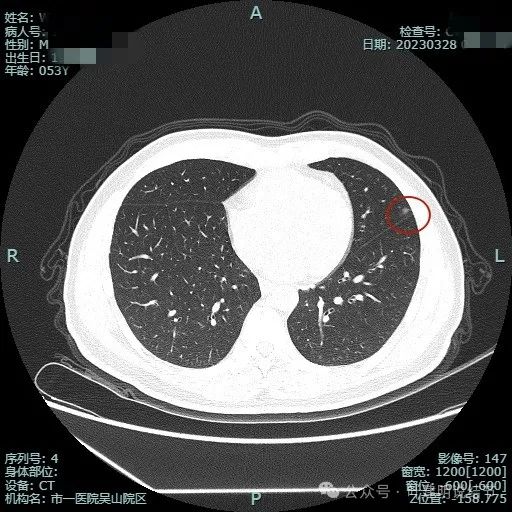

2023年3月影像展示:

密度纯,但不是太均匀,感觉稍不均,瘤肺边界清,贴胸膜近。

与叶间裂也是贴着的。

靶重建后见病灶密度不是很淡,轮廓较清,离叶间裂近但未见明显牵拉。

上图层面病灶贴着叶间裂,轮廓与瘤肺边界清楚,表面不光滑。